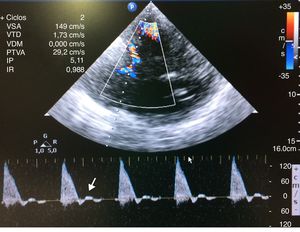

Mujer de 43 años con cefalea brusca. La TC demuestra hemorragia parieto-occipital izquierda sobre lesión subyacente con herniación parcial. La escala de coma de Glasgow (GCS) 15 hasta el 4.° día, en el que presenta anisocoria derecha y GCS 3. Se inicia osmoterapia, sedación, VM, hiperventilación y catéter en subclavia derecha, resolviéndose la anisocoria y siendo el valor de BIS 40 (se descarta resangrado en la TC). A los pocos minutos se implanta sensor de PIC (65mmHg), BIS cae a 0 y el Doppler transcraneal objetiva flujo sistólico con ausencia de onda diastólica (fig. 1), que no revierten con medidas de 1.° nivel. Descartadas otras etiologías de hiperPIC, se realiza Rx de tórax de control de vía, aún pendiente, objetivándose neumotórax (NT) derecho iatrogénico a tensión. Tras drenar NT, se normalizan pupilas, velocidades de la ACM (fig. 2), BIS y PIC.